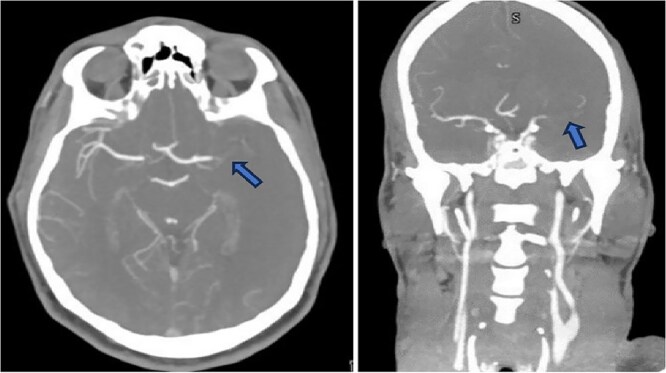

Malignant Middle cerebral artery (MCA) infarction is characterized by rapid neurological deterioration due to cerebral edema. Spasticity, a common sequela of stroke, typically occurs days to weeks after the initial event. However, an acute onset of spasticity at presentation is extremely rare. We report a case of a 40-year-old male patient who presented with spasticity accompanied by aphasia and decreased consciousness. Left MCA occlusion was demonstrated on Computed tomography (CT) angiography. Cerebral edema developed rapidly, requiring decompressive hemicraniectomy (DH). The patient was a known smoker with androgenic anabolic steroid use. This case represents a rare presentation of malignant MCA infarction with acute spasticity and adds a unique aspect to the clinical spectrum of stroke presentation. This case emphasizes the need for awareness of atypical stroke presentation and the potential role of anabolic steroids in stroke risk.